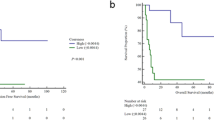

With a cox proportional hazard model, clinical features, treatment scheme, TV, SUVmax, MTV and TLG at any threshold, were not significantly associated with DFS in univariate analysis (Table 2). The significant features in the univariate and multivariate analyses are listed in Table 3. As features were standardised before performing the Cox regression, the hazard ratio units correspond to standard deviations of the different covariates. The most significant features were textural (GLDZM and GLSZM). Figure 2 shows the Kaplan-Meier curves for each of the significant individual features. The threshold for each feature was defined through the Youden Index of the feature ROC curve in the training data. GLSZM_HILAE_0.5 (TLR) was the only feature providing statistically different stratification between the two Kaplan-Meier curves, according to the log-rank test.

Kaplan-Meier curve of the each individual significant feature in univariate and multivariate analysis, after the Cox proportional hazard model. a GLDZM_DZNN_0.5 (OR) (Threshold = 0.59, log-rank test P value 0.079). b GLSZM_HILAE_0.5 (TLR) (Threshold = 0.07, log-rank test P value 0.044), c GLDZM_DZV_0.05 (TLR from interpolated images) (Threshold = 1.28, log-rank test P value 0.47). d Stats_qcod_0.2 (TLR from interpolated images) (Threshold = 1.18, log-rank test P value 0.088). e Histology (Threshold = 0.5, log-rank test P value 0.15)

Figure 3 shows the Kaplan-Meier curves of the best OR and TLR models, which were significantly discriminant: log-rank P value of 0.034 for the OR and 0.002 for the TLR model. Both models performed better than the individual radiomic features. The differences between AUC and precision of the OR and TLR models were however not statistically significant (P value = 0.64 and 0.34 respectively).

Kaplan-Meier curve of the test set for the best OR (a) and TLR (b) model. Red and blue curves represent respectively patients with better and worse prognosis. The log-rank test was used to estimate statistical significance of the difference between survival curves. The P value obtained from the log-rank test is shown in the left down corner of each image. The difference between both the Kaplan-Meier curves is statistical significant (log-rank P value = 0.034 for the OR model and 0.002 for the TLR model)